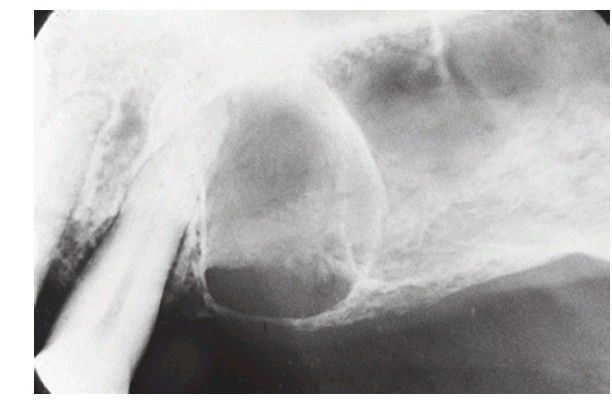

Radiograph of cyst

Typical radiographic appearance of cyst. The radiolucent center is surrounded by a zone of reactive bone (condensing osteitis)